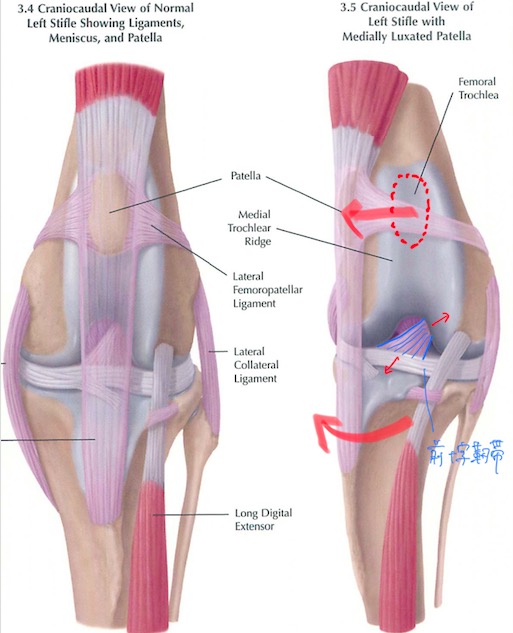

膝蓋骨内方脱臼パテラを併発した前十字靭帯損傷・断裂の犬の1例(整形外科、膝、パテラ、TPLO、手術)

膝蓋骨(パテラ、膝のお皿の骨)の脱臼は犬で最も多く見られる整形外科疾患の1つであり、その多くは生まれ持っての解剖学的な問題による先天性のものです。稀ではありますが猫でも見られます。

日常的に膝蓋骨が脱臼する子は常に膝が内側に引っ張られるような力がかかっており、膝の中にある前十字靭帯に過剰な負荷がかかっていることが多くあります。(赤矢印)

年齢を重ねるごとに靭帯は弱ってしまうため、このような状態が続くとある日前十字靭帯が損傷・断裂してしまうことがあります。

前十字靭帯が損傷すると膝関節が不安定になり、ももの骨とすねの骨が前後にずれるような状態になります。

これによりうまく体重を支えられなくなり、多くの子は足を着けなくなってしまいます。